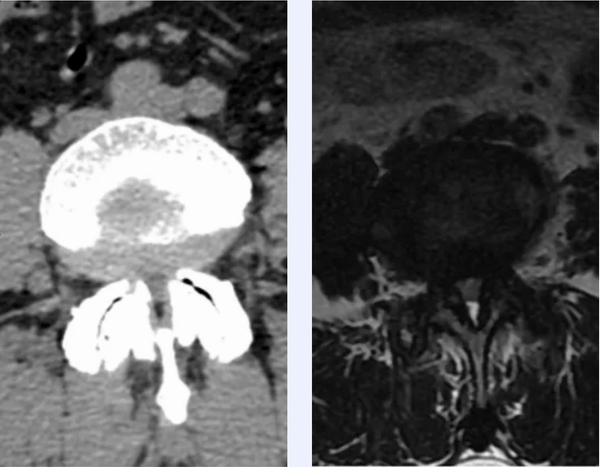

楊峻主任團(tuán)隊(duì)結(jié)合患者癥狀體征及影像檢查考慮患者為腰椎退變滑脫、重度椎管狹窄,脊髓神經(jīng)明顯受壓,導(dǎo)致腰骶和下肢疼麻及活動受限等病癥,需要予患者行椎管徹底減壓,解除脊髓神經(jīng)受壓,同時行融合內(nèi)固定。詳細(xì)閱讀相關(guān)影像結(jié)果,該患者腰椎增生退變及椎管狹窄較重,同時腰段椎體旋轉(zhuǎn)帶側(cè)凸,可導(dǎo)致術(shù)中解剖結(jié)構(gòu)辨識困難,脊髓神經(jīng)比鄰關(guān)系不清,手術(shù)難度大,風(fēng)險(xiǎn)高,手術(shù)復(fù)雜。為保證手術(shù)的安全性及精準(zhǔn)手術(shù)操作,防止損傷脊髓神經(jīng),降低手術(shù)風(fēng)險(xiǎn),楊峻主任團(tuán)隊(duì)決定借助最先進(jìn)的3D數(shù)字打印技術(shù)為其實(shí)施腰椎減壓融合內(nèi)固定術(shù)。

通過采集患者術(shù)前數(shù)字影像結(jié)果,利用醫(yī)學(xué)3D打印技術(shù)基于患者的個體情況,設(shè)計(jì)并打印出患者腰椎退變模型及椎弓根螺釘置釘導(dǎo)板。利用模型進(jìn)行術(shù)前規(guī)劃和手術(shù)模擬,對手術(shù)中的難點(diǎn)和重點(diǎn),如導(dǎo)板預(yù)置方案、截骨減壓矯形策略等反復(fù)推演,保證手術(shù)的安全性及精準(zhǔn)手術(shù)操作,防止損傷脊髓神經(jīng)。